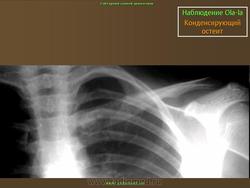

Склерозирующий остеомиелит из ключицы впервые был описан как заболевание лица в 1974 году. Существует боли и часто локализуется опухоль из медиальной трети ключицы, с повышенной плотностью радио.Sternoclavicular совместных, как правило, никогда не занимался. Он также известен как асептический расширения остеосклероз из медиального конца ключицы.

Это редкое заболевание, чаще всего видели у женщин позднего репродуктивного возраста. К тому времени пациентов диагностируется состояние и симптомы будут присутствовать в течение нескольких месяцев или лет. Боль описывается как прерывистое или постоянно, но время от времени могут быть интенсивными. Боль обычно локализуется в медиальнойконца ключицы, но может излучать в плечо, шею и передней грудной стенки.Движение плеча редко ограничивается, но крайней сгибание и похищение может усугубить боль. Опухолью по медиальной ключицы часто присутствует, не покрывающей изменений кожи. Воспаление кожи обычно обозначает инфекции. Нежность мягкий. Bi боковой участия не сообщалось.

Множественные мелкие и крупные (до 10 мм) очаги остеосклероза округлой или овальной формы, расположенные в эпифизах трубчатых костей, а также в других костях, за исключением ключицы.